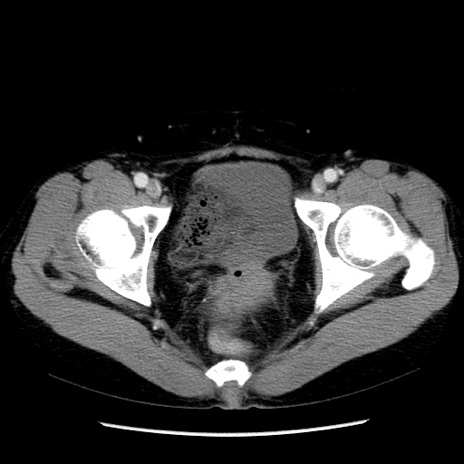

症例6(横断像)

【症例】50歳代女性

【主訴】下腹部痛

【現病歴】本日朝より下痢2回あり。 昼食を食べた後、嘔吐3回、下腹部痛認め、症状軽快せず、当院救急搬送。

【既往歴】卵巣癌術後(8年前に当院で卵巣摘出)

【身体所見】 意識清明、腹部:平坦、腸蠕動音→、やや硬、下腹部自発痛・圧痛あり、反跳痛あり、筋性防御なし。

【データ】WBC 16000、CRP 0.01